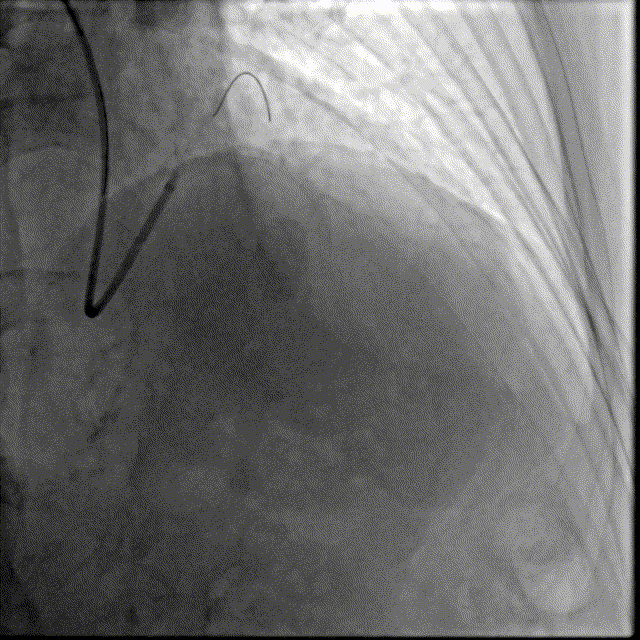

选择EBU指引导管,以2.0预扩张球囊及2.5×12mm耐高压球囊预扩前降支近段病变,可见不同程度的球囊膨胀欠佳。

冲击波导管送至左前降支,由中段至开口依次以4atm压力初始冲击扩张,6atm压力巩固扩张,共冲击扩张10秒×8个周期,可见球囊逐渐膨胀充分。此阶段在处理前降支开口时预置回旋支保护导丝。